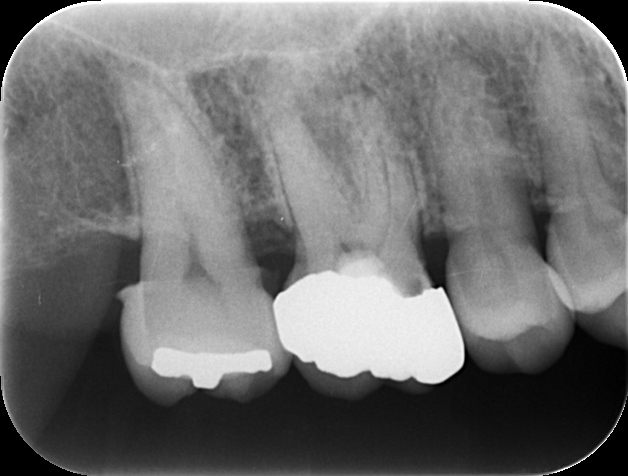

| 相談内容 | 右上の奥歯で固いものが咬めない、歯茎から血が出るとのことで来院されました。 |

| カウンセリング | 中等度歯周病であり、根の病気にもなっていました。 |

| 治療内容 | 根管治療後、歯石を確実に取り骨の形を整えるために歯周外科手術を行いました。 その後、型取りを精密に行いセラミック修復を行いました。 |

| 治療後 | 術後の経過は良好で、根の病気も完治しメンテナンスに移行しました。 |